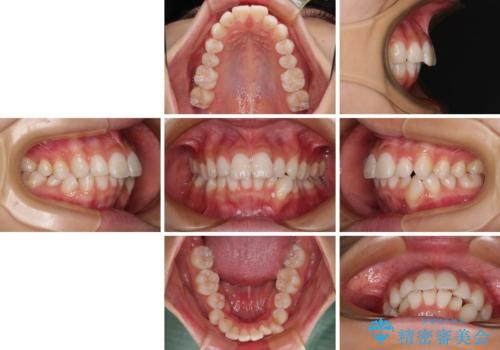

- 口を閉じたときに飛び出してしまう上顎前歯を気にして来院された患者様です。

下顎はデコボコが気になっていたため、上下左右第一小臼歯4本を抜去して、ワイヤー装置にて口元の突出感を改善するよう矯正治療を行うこととしました。